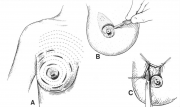

| 15:48, 8 בספטמבר 2012 | שיטותפולשניות1.jpg (קובץ) |  |

9 קילו־בייטים | Nachi | 1 | |

| 15:49, 8 בספטמבר 2012 | שיטותפולשניות2.jpg (קובץ) |  |

15 קילו־בייטים | Nachi | 1 | |

| 15:49, 8 בספטמבר 2012 | שיטותפולשניות3.jpg (קובץ) |  |

10 קילו־בייטים | Nachi | 1 | |

| 15:50, 8 בספטמבר 2012 | שיטותפולשניות4.jpg (קובץ) |  |

5 קילו־בייטים | Nachi | 1 | |

| 15:50, 8 בספטמבר 2012 | שיטותפולשניות5.jpg (קובץ) |  |

7 קילו־בייטים | Nachi | 1 | |

| 15:50, 8 בספטמבר 2012 | שיטותפולשניות6.jpg (קובץ) |  |

7 קילו־בייטים | Nachi | 1 | |